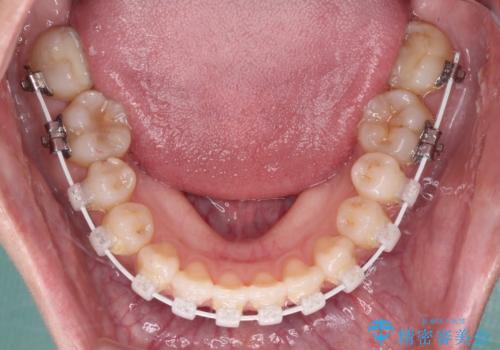

前歯のクロスバイトを治したい ワイヤー装置による矯正治療

- 前歯の反対咬合を気にして来院された患者様です。

マウスピース矯正も提案しましたが、しっかりと使用する自信がないとのことで、ワイヤー装置により矯正治療を行うこととしました。

クロスバイト改善まではスムーズに進みましたが、その後は強い舌の突出癖によりオープンバイトの期間が長く続きました。

舌のトレーニングをしっかりと実施してもらい、何とか仕上げることができました。